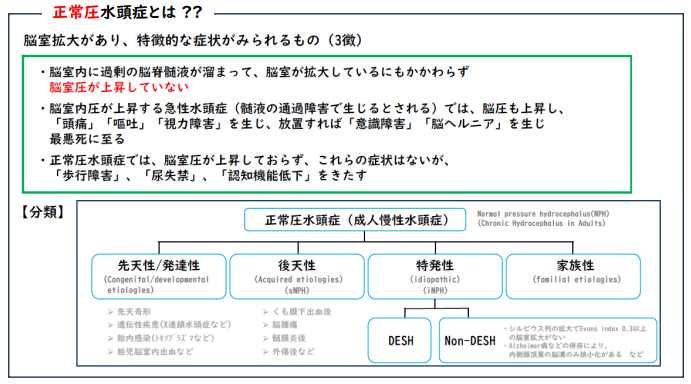

正常圧水頭症とは髄液圧が正常のものをいい、脳の圧が上がらないため命に係わることはありませんが、生活に影響する症状を起こしてきます。正常圧水頭症は、「先天性」「二次性(くも膜下出血後、髄膜炎後、外傷後など)」「特発性」「家族性」に分類されています。

特発性とは明らかな原因がないのに水頭症を来すもので、高齢者に多く見られます。年間10万人あたり120人程の方がこの「特発性正常圧水頭症」になると言われていますが、実際受診される患者は発症者の10%未満といわれており、診断されていない患者さんが多いとされています。